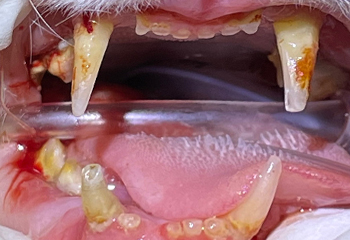

고양이 구내염

Feline Chronic Gingivostomatitis

잇몸뿐 아니라 목구멍주변까지 염증이 발생하며 심한 통증을 유발하는 질환입니다.

침흘림, 식욕부진, 심한구취 등을 동반할수 있으며 흔히 치주질환을 동반합니다.

구강내 치석과 세균증식을 최소화 하기위해서 일반적으로 약물처치 이후 전체적인 구강내 치아발치를 요하게 됩니다.

약 70-80%가량의 고양이에서 발치후 구내염의 증상이 완화되며 단순한 위생적인 문제뿐아니라 현저한 삶의질 저하를 유발하기 때문에

반드시 치료가 필요한 질환입니다.

구내염 치료 사례

치료 전

치료 전

치료 전